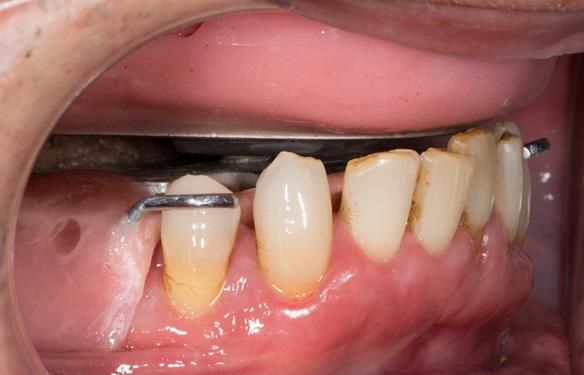

This newsletter describes in step by step detail the transition from acrylic based immediate dentures to metal based definitive dentures.

- Definitive dentures (Mk 2) – complete upper metal reinforced and lower cobalt chromium based partial of hygienic Scandinavian design to be made 9 - 12 months after extractions of all upper teeth and LR5 and LL4

The clinical situation and treatment process is shown in detail below with photographs.